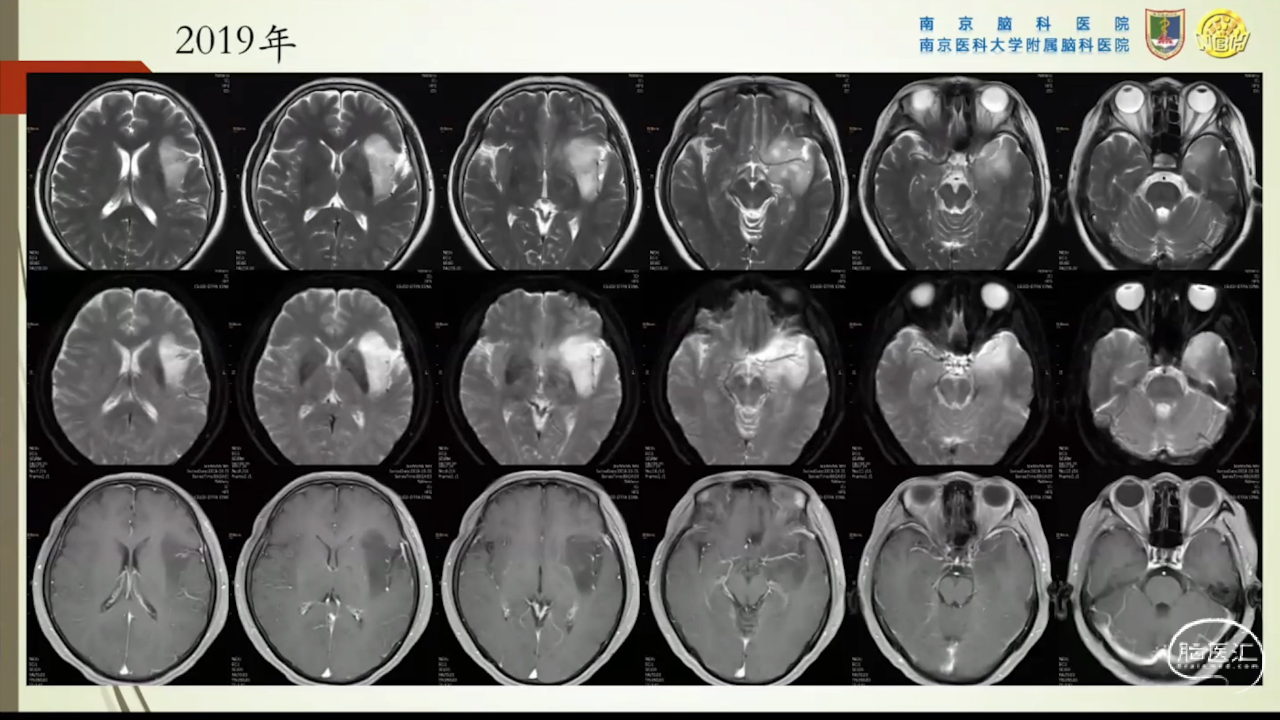

胶质瘤是发病率最高的颅内肿瘤(约占44.69%),岛叶是神经胶质瘤的好发部位,大约有25%的低级别胶质瘤及10%的高级别胶质瘤发生在岛叶,大多数岛叶胶质瘤为低级别胶质瘤。岛叶在调节内脏感觉运动、控制心血管交感活性、传入躯体感觉中均起重要作用。它也参与了痛觉的传递、运动规划、自主性吞咽、味觉、听觉、前庭功能、情绪、认知能力和语言能力。因为岛叶解剖结构复杂,并覆盖有高级语言皮层、白质束及重要的血管结构,故岛叶部位的手术难度极大。

讲题岛叶胶质瘤的显微手术治疗